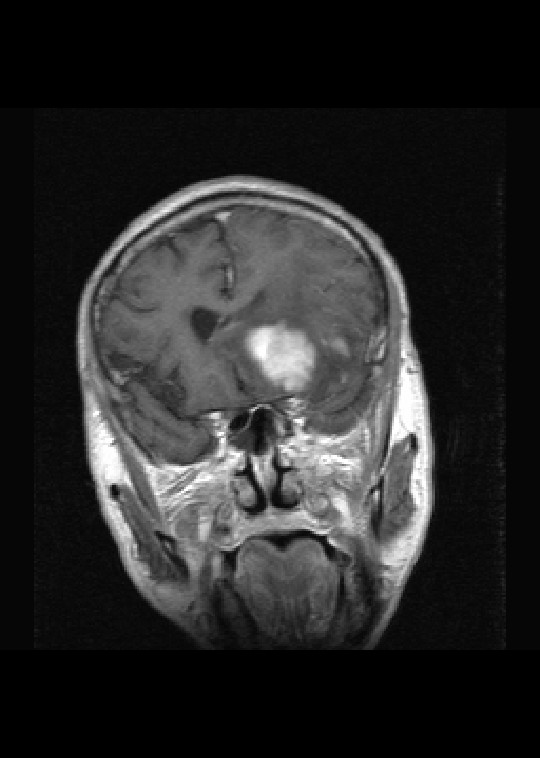

(左额颞叶)非霍奇金淋巴瘤,b细胞性,弥漫性大b细胞型。免疫组化结果:cd45(lca) +,vimentin +,ck(ae1/ae3) -,ema -,cd3 -,cd20 +++,cd30 -,plap -,cd79a +,gfap -,alk -,s-100 -。

左侧基底节区病灶t1wi呈不均匀稍低信号,t2wi呈稍高信号,周围伴有水肿。增强扫描呈均匀团块样或者抱拳样明显强化,相邻的柔脑膜亦见线样强化。首先考虑淋巴瘤。可惜没有ct平扫,如果ct平扫病灶呈高密度,那么更支持pcnsl的诊断。

病理结果:(左额颞叶)非霍奇金淋巴瘤,b细胞性,弥漫性大b细胞型。免疫组化结果:cd45(lca) +,vimentin +,ck(ae1/ae3) -,ema -,cd3 -,cd20 +++,cd30 -,plap -,cd79a +,gfap -,alk -,s-100 -。

左侧基底节区病灶t1wi呈不均匀稍低信号,t2wi呈稍高信号,周围伴有水肿。增强扫描呈均匀团块样或者抱拳样明显强化,首先考虑淋巴瘤。